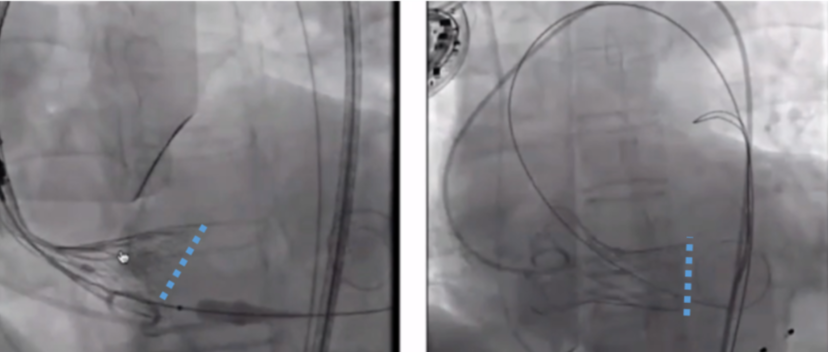

冯沅教授则结合精彩的手术案例,分享了VitaFlow Liberty™对于极度横位心的应用体会, 以及通过“反推”技巧获得更好的同轴效果。

该案例患者为64岁女性存在超级大横位心且左室心肌明显增厚、心腔小的症状。术中观察主动脉瓣根部造影,用20 mm球囊进行预扩,复查造影时瓣叶刚好打开且无明显腰征,遂用圈套器辅助VitaFlow®24mm瓣膜跨瓣,以较保守措施进行低位释放。

图片

第一次瓣膜释放

第一次瓣膜释放位置较深,遂将瓣膜部分回收拉高后重新定位并“反推"帮助瓣膜调轴后完成释放,完成后,造影显示瓣膜植入深度较好,未出现明显瓣周漏。

第一次释放位置较深

二次释放时反推-同轴效果明显

"反推"操作特别适合类似于VitaFlow®这种质地的瓣膜,也是区别于其他瓣膜的一大优势。植入位置合适时,可以通过前推VitaFlow®瓣膜瓣架使其打弯,接近大弯侧。在反推过程中,可以使瓣膜左边上提,右边下降,进而形成更佳的瓣膜轴向。但若遇到反推后瓣膜两边都下降的情况,一般是因为植入的瓣膜尺寸较小,锚定不牢固,此时便需要回收瓣膜,更换较大尺寸瓣膜进行再次释放。

对于该患者,术后即刻造影示瓣膜植入深度较好,没有明显瓣周漏,因瓣膜并无钙化,未进行球囊后扩。术后超声示主动脉瓣瓣口流速2.3 m/s,主动脉瓣跨瓣压差12 mmHg,无二尖瓣、三尖瓣反流。